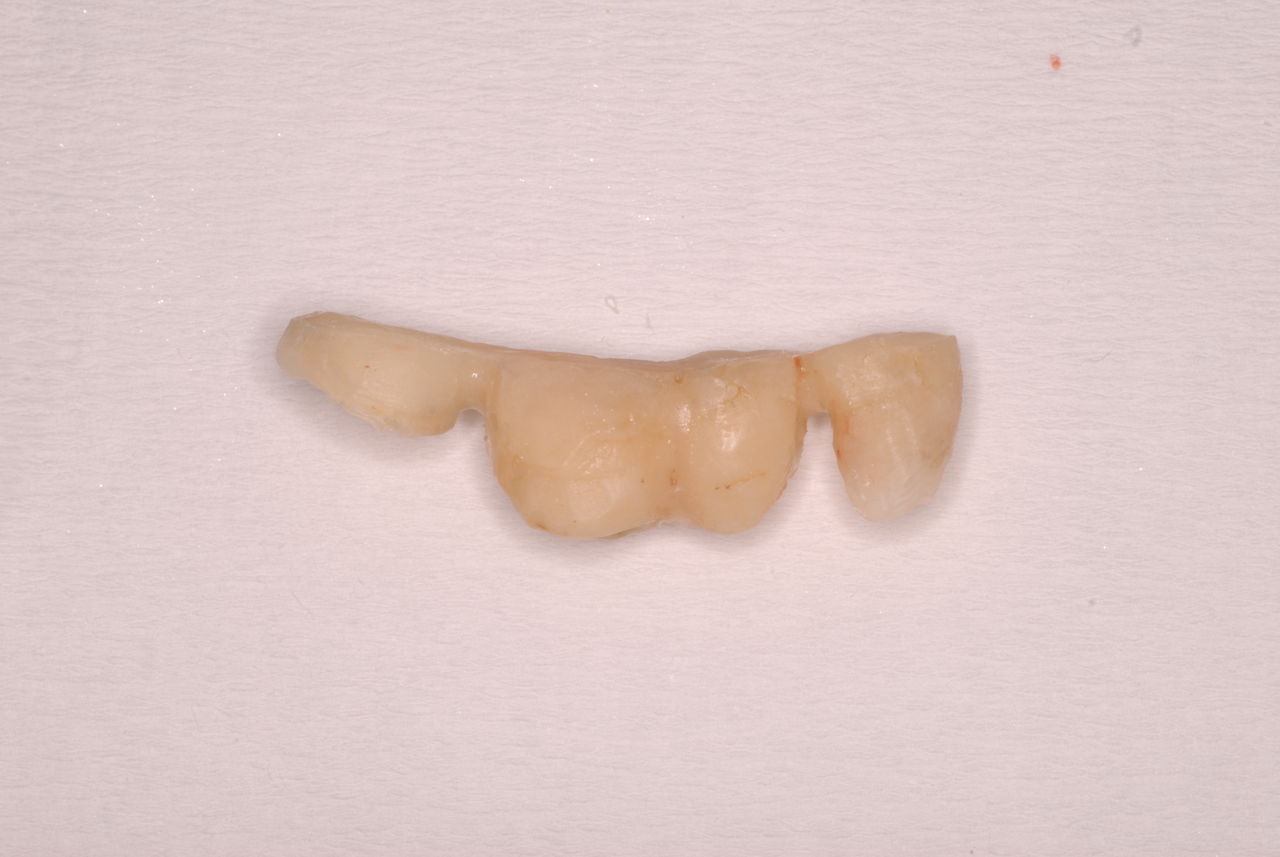

なかなかブラシの使い方ができていないようで、歯磨きと歯周病でのブラシの使い方は別なのですが、習ったことも検査もされずに金属を被せたりしているようで、これからも歯医者さんで抜かれたり、その後にインプラントのような高価な“クギ”を打ち込まれる方が増えるかと思うと残念です。

被せても、詰めても病気は治らないのですから。又病気の元になり易い不適合な差し歯や金属、インプラントがあればそこからバイキンが侵入して体に悪さもしやすいのではないかと心配しています。

お口の中から差し歯、入れ歯、詰め物を追放しましょう!

口の中の病気を治し、病気を興さない医療を目指します。

二度とお口の中へ変なものを入れなくても済むように

予防に精進いたしましょう!安全な矯正、美容を目指しましょう!